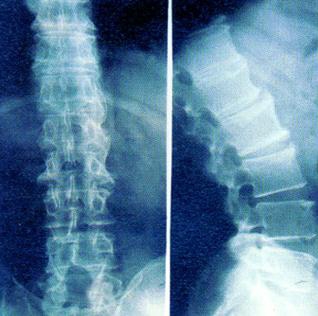

强直性脊柱炎是一种很严重的骨科类疾病,它的严重性不仅体现在本身的病症上面,还会有一些其他的并发症状,严重危及人体的日常生活。它对人体关节所造成的损伤是大的,那么强直性脊柱炎具体有哪些表现呢?我们请 贵阳风湿病中医院 的专家来为大家介绍: 强...[详细] 2016-01-09

我们知道强直性脊柱炎是一种全身性的免疫类疾病,如果不能及时的加以治疗,会造成一系列的并发症危害着我们的身体。那么强直性脊柱炎会引起哪些并发症的发生呢?下面我们请 贵阳风湿病医院 的专家来为大家介绍一下吧: ⑴骶髂关节炎:有超过90%的强直性脊柱炎...[详细] 2016-01-08

强直性脊柱炎对人体造成的伤害是方方面面的,而且不及时加以治疗,更加会引发一系列的并发症。如果任其发展更加会引发骨头坏死,造成骨骼的严重损伤。那么强直性脊柱炎是怎么引发骨头坏死的呢?我们请 贵阳风湿病医院 的专家来为大家解答吧: 强直性脊柱炎是...[详细] 2016-01-06

强直性脊柱炎对人体的伤害有多大我想大家都是知道的,但是有时候强直性脊柱炎的危害不仅仅是对身体上的,还有其他的种种方面,所以希望大家能够重视起来。下面我们请贵阳风湿病医院的专家来为大家介绍一下 强直性脊柱炎对人体造成的危害 : 强直性脊柱炎的危...[详细] 2016-01-04